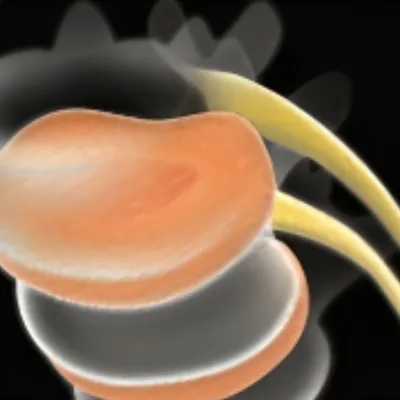

Our Advanced Laser-Enhanced Spinal Decompression™ Therapy is designed to gently stretch the spine, creating negative pressure within the discs. This process encourages the retraction of bulging or herniated discs and promotes the influx of healing nutrients, reducing inflammation and pain. Our unique methods relieve tension and pressure on the spinal discs, moving the affected parts of the spine back to their natural position. Additionally, the increased blood flow introduces more nutrients to the discs, promoting healing from within and significantly improving patient outcomes.

4) Reduces pressure on nerves

Our treatment technique targets your spinal nerves at the source to generate new cartilage and reduce inflammation and swelling around affected discs and joints, enabling damaged tissue to repair itself faster than usual. This is such a relaxing & painless process, that most of our patients fall asleep during their session!